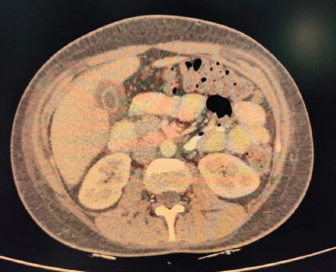

Inflammatory workup revealed: ESR–22 mm Hg in 1 hour, CRP–53.2 mg/dl, Procalcitonin–1.92 ng/ml. D dimer–1.9 mg/l. Ferritin–2,500 ng/ml. Chest X-ray revealed blunting of bilateral costophrenic angles suggestive of bilateral pleural effusion (Fig. 1).

Fig. 1. X-ray showing blunting of bilateral costophrenic angles (Right > left) suggestive of pleural effusion.